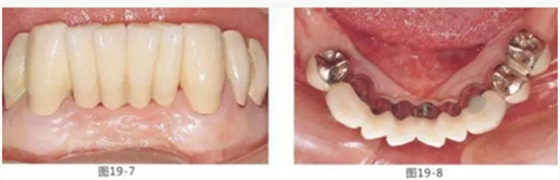

圖19-7 佩戴最終修復5年后的唇頰側面照。

圖19-8 同時期下側咬合面照。